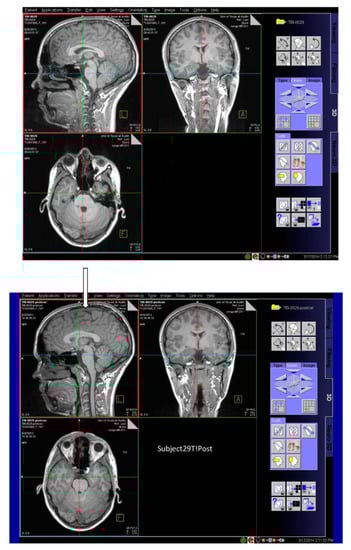

The most readily observed changes were increases in the width of the sulci in many of the players, as illustrated in Figure 1. The most profound changes appeared in the athletes who had experienced concussive events but the sulci were also widened in the soccer players who did not have reported concussions. Because we observed increases in width of the sulci in players, the changes in brain volume of each individual athlete were calculated to quantify the changes as described in the Methods section. The changes in the calculated longitudinal relative total brain volume of seven athletes over the years is shown in Figure 2. In addition to the widening of the sulci in the frontal, parietal, and occipital regions of the brain, we observed low-intensity punctate regions in the white matter interfaces on T2- and susceptibility-weighted images associated with the base of the sulci (Figure 3). Four of the players imaged over four years exhibited reductions in brain volume (Athletes 10, 11, 12, 15) while the remaining athletes exhibited no change in relative brain volume over the multiyear period. Only one of the players with reduced brain volume, Athlete 15, sustained a concussive event while the other three did not have reported concussions. She had a concussion during her first year at the University. An additional athlete (Player 29) was evaluated using MRI (Figure 4, pre- and post-concussion) and the IMPACT tool following the concussion and then again four days later. The MRI revealed increases in the sulcal volume in the region of the pre- to post-central sulci following the concussive event. Athlete 29 was not imaged for four consecutive years and so was not included in Figure 2. From these observations, it appears that overt concussive events are not required for there to be a reduction in brain volume. The reduction of two percent in the longitudinal relative brain volume of the four athletes is unusual when compared with the metadata analysis reported in Hedman et al. []. The brain volume in normal women between the ages of 18 and 25 generally increases two to three percent or remains the same during this developmental stage; this is the age range of athletes in our study.

Figure 4.

Images in three planes of a woman athlete before concussive event (upper image); three planes of images of the same athlete several days after concussive event (lower image). The widened sulci under the arrow in the region of the pre- to post-central sulci after concussion are visible compared with the preconcussion image in (upper image).